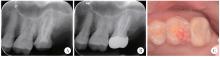

Figure 1

Intraoral examination, preoperative radiograph and cone-beam CT images of left maxillary second molar A, preoperative intraoral view of apical swelling (white arrow); B, preoperative periapical radiograph shows a metallic high-density fractured instrument (red arrow) within the mesiobuccal canal; C, the clinical view after crown removal reveals a resin filling and a palatal fiber post (white arrow); D, the palatal post extends to the mid-root level with an apical radiolucency; E, the image confirms the separated instrument in the apical third of the mesiobuccal root, associated with an apical radiolucency communicating with the distobuccal apical lesion; F, underfilled obturation is observed in the distobuccal root canal. P, palatal; MB, mesiobuccal; DB, distobuccal."